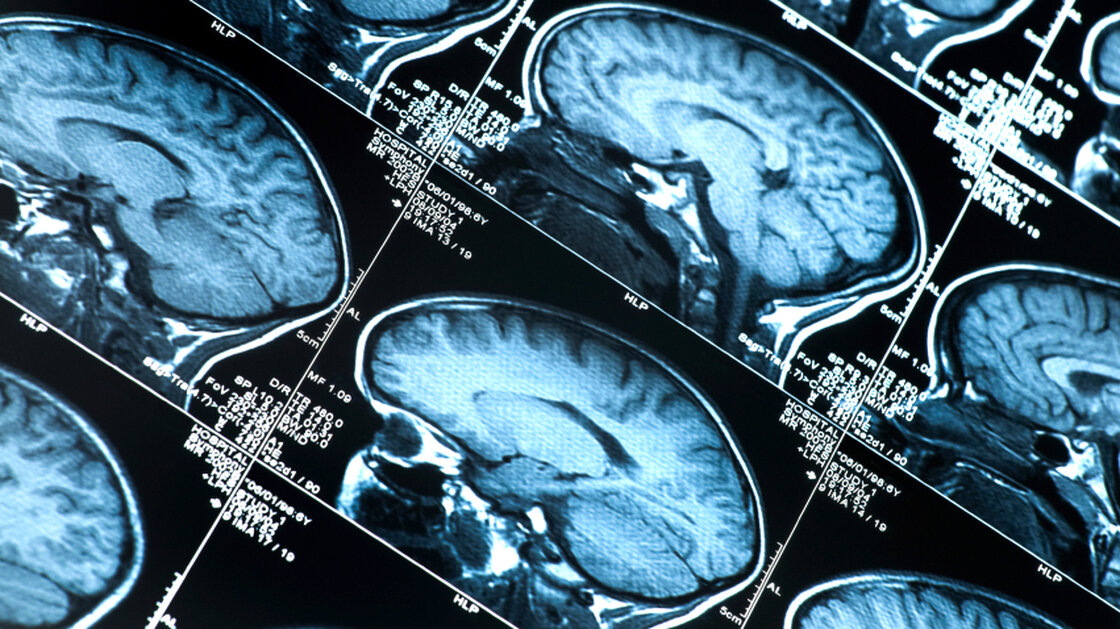

Doctors may eventually be able to diagnose "preclinical" Alzheimer's in patients who have abnormal brain scans but who aren't yet showing behavioral symptoms of the disease.

The goal is to eventually allow doctors to diagnose "preclinical" Alzheimer's in patients who do not have problems with memory or thinking, but who do have an abnormal brain scan or some other sign that the disease may be developing.

It's becoming possible to detect those signs of trouble using brain scans, tests of spinal fluid or , and other so-called biomarkers, Carrillo says. These markers "can tell us that underlying biology is really changing in the body before memory starts to change," she says.